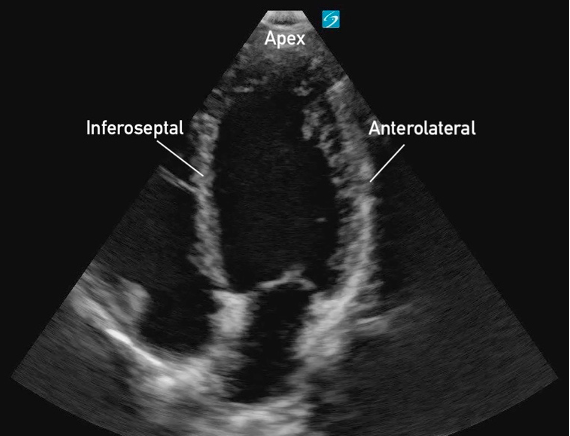

Apical Four Chamber

What am I Looking at?

In A4C view, you can assess LV wall motion at the basal, mid, and apical levels of the inferoseptal and anterolateral walls (figure 19). This view is also useful for visual estimation of overall contractility and evaluation of the LV’s size and shape throughout systole and diastole.

It is important to avoid foreshortening in the A4C view, as this can underestimate LV length and overestimate function. If the LV appears round or blunt at the apex, the image is likely foreshortened—slide the probe laterally and slightly inferiorly to better align with the cardiac apex, and angle it more anteriorly (toward the face) to bring the true apex into view and ensure a full-length chamber.

Figure 19: Apical 4 Chamber view in cardiology convention with the labeled left ventricular walls

What is Normal

Contractility:

The apex and visible LV walls (inferoseptal and anterolateral) should move inward toward the center, with the base also moving toward the apex. All walls should demonstrate coordinated inward motion and uniform thickening.

Eyeballing Ejection Fraction:

When qualitatively assessing LV function in the A4C view, the EF can often be ‘eyeballed’. The LV cavity should visibly reduce its volume by more than half with each contraction. Longitudinal shortening will also contribute to overall cavity reduction.

RWMAs:

RWMAs may be observed in the inferoseptal wall, anterolateral wall, or apex, with segments showing hypokinesis, paradoxical motion, dyskinesis or akinesis while other segments contract normally (figure 23). The segments may also be reduced in a global fashion.

Figure 23: A4C view demonstrating moderately reduced LF systolic function and RWMAs of the inferoseptal and anterolateral walls.

Hyperdynamic function:

The inferoseptal and anterolateral walls may nearly or completely touch during systole, leading to near obliteration of the ventricular cavity (figure 24). This effect is often more pronounced at the apex, while the basal segments may not completely obliterate.

Figure 24. A4C view demonstrating hyperdynamic LV systolic function.